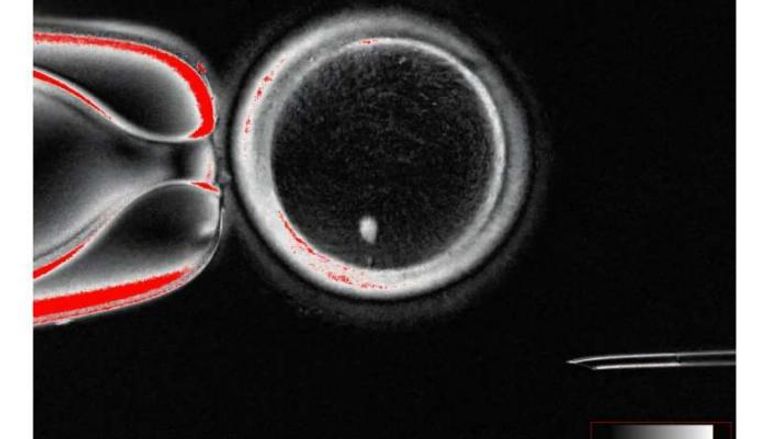

وباستخدام هذه الآلية، تمكن الباحثون من إعادة برمجة نواة خلية جلدية وزرعها في بويضة منزوعة النواة. وعند تحفيزها داخل البويضة، تخلصت النواة من نصف كروموسوماتها لتصبح بويضة تحمل العدد الصحيح (23 كروموسوما)، ثم جرى تخصيبها بالحيوانات المنوية عبر التلقيح الصناعي .

ونجح الفريق في إنتاج 82 بويضة وظيفية، تم تخصيبها جميعا، لكن عددا قليلا منها (9%) فقط وصل إلى مرحلة الكيسة الأريمية (Blastocyst) بعد ستة أيام، وهي المرحلة التي تُعتبر حاسمة في عمليات أطفال الأنابيب.